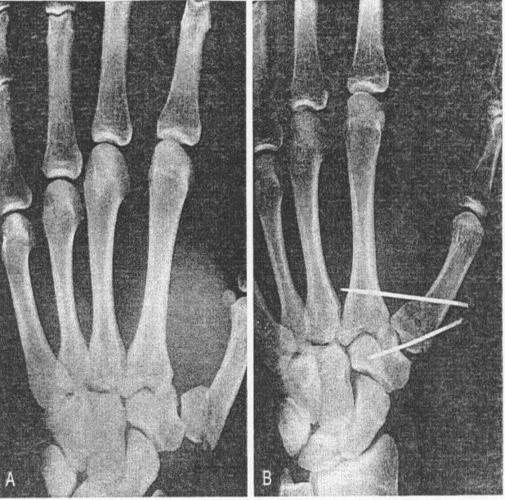

固定于大多角骨上;2,内侧有较大骨折块时-将其直接固定在第一掌骨上;1